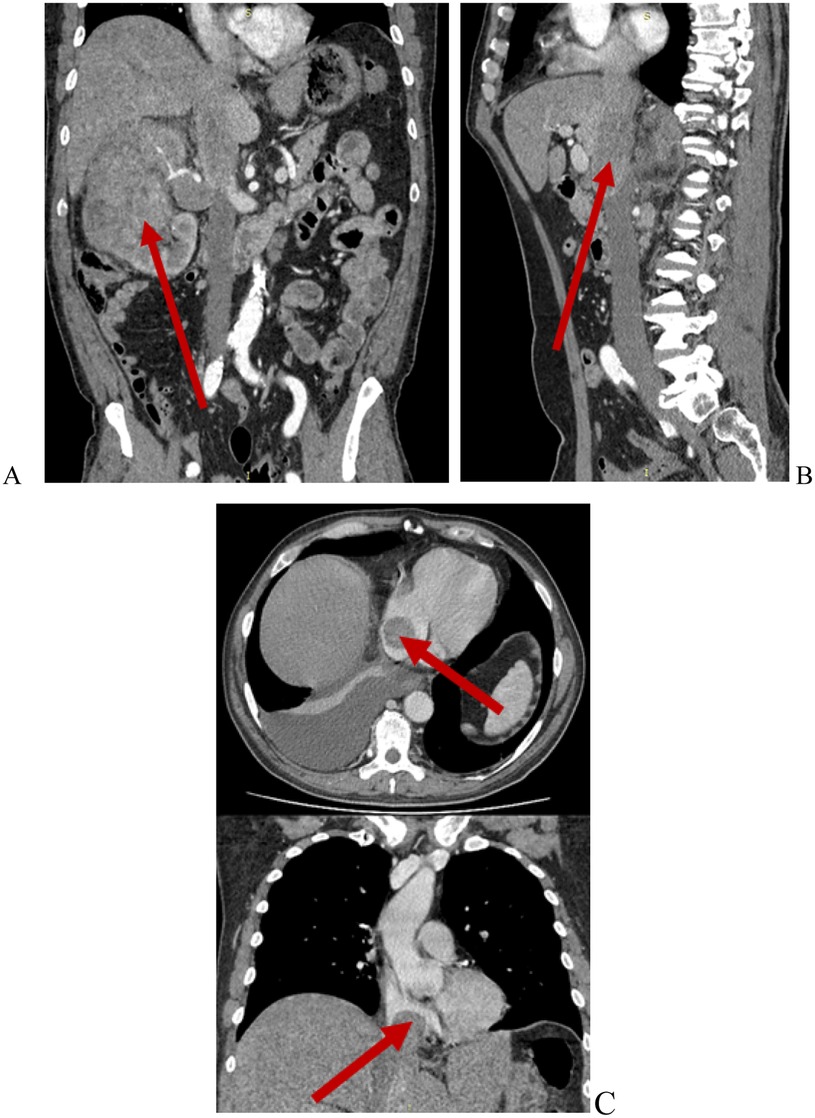

AbstractBackground:Tumor thrombus extending into the inferior vena cava (IVC) in patients with renal cell carcinoma (RCC), particularly at Mayo levels III and IV, presents a major surgical challenge. Although systemic treatments are evolving, surgery remains the mainstay of management. The role of cardiopulmonary bypass (CPB) in this setting is not clearly defined.Methods:We retrospectively analyzed 20 patients with RCC and Mayo level III–IV IVC tumor thrombus who underwent radical nephrectomy with IVC thrombectomy at our center between 2017 and 2024. Preoperative workup included MRI, contrast-enhanced CT, and transthoracic/transesophageal echocardiography. CPB was used selectively in five patients with tumor extension into and adherence to the right atrium. Postoperative complications were classified using the Clavien–Dindo system. Survival was assessed with Kaplan–Meier analysis and Cox regression.Results:Median age was 61 years (IQR 51–72), and 70% were male. Level IV thrombus was present in 60% of patients, and 40% had distant metastases. Median operative time was 370 minutes and median blood loss was 2,500 mL. Postoperative complications occurred in 20% of patients, with one in-hospital death (5%). Median hospital stay was 11 days. The 1-, 3-, and 5-year overall survival rates were 66.7%, 41.6%, and 34.6%, respectively. Distant metastases were associated with lower survival (HR 2.48; p = 0.005), while immuno-targeted therapy improved outcomes (HR 0.69; p = 0.035).Conclusion:Radical nephrectomy with IVC thrombectomy in patients with advanced tumor thrombus can be performed safely with good long-term outcomes in selected cases. Careful preoperative imaging, intraoperative echocardiography, and the selective use of CPB are key to minimizing risks. These findings support a tailored surgical approach based on thrombus level and clinical condition. Further prospective studies are needed to refine surgical indications and clarify the role of systemic therapy.